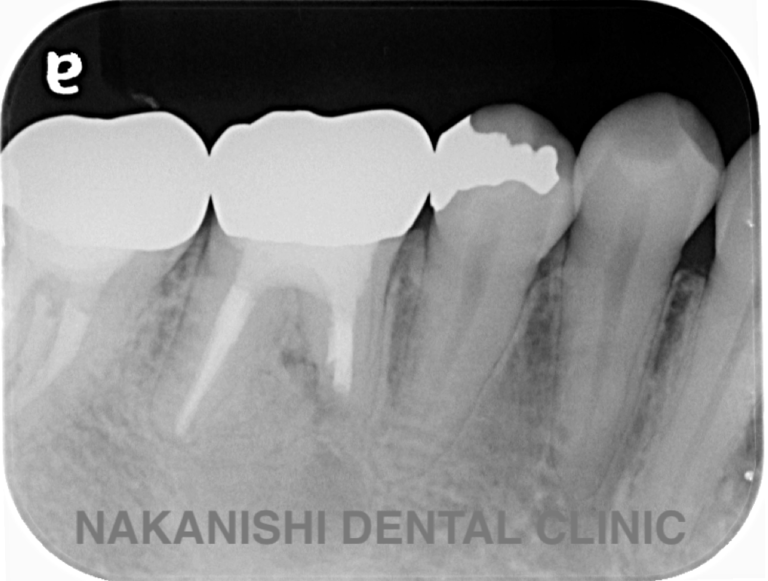

case 4.

治療前

治療後

| 主訴 | 右下奥歯が痛い。 他院で『膿の袋が大きいため抜歯』と言われセカンドオピニオン希望でご来院。 |

|---|---|

| 治療期間 | 約半年(6か月) |

| 治療費 | 約5万円 |

| 治療内容 | ラバーダム、マイクロスコープ下にて根管治療を実施し、歯根端切除を行う。歯茎の腫れは消失し違和感や痛みも消失した。 |

| 治療のリスク | マイクロスコープやCTを使用し、可能な限り精密な根管治療を行っていますが、歯根の形態や病変の大きさ、過去の治療履歴などにより、治癒が得られない場合があります。 また、治療後に再感染や歯根破折が生じることもあり、その場合は再治療や抜歯が必要となることがあります。 治療結果には個人差があり、すべての症例で同様の経過を保証するものではありません。 |